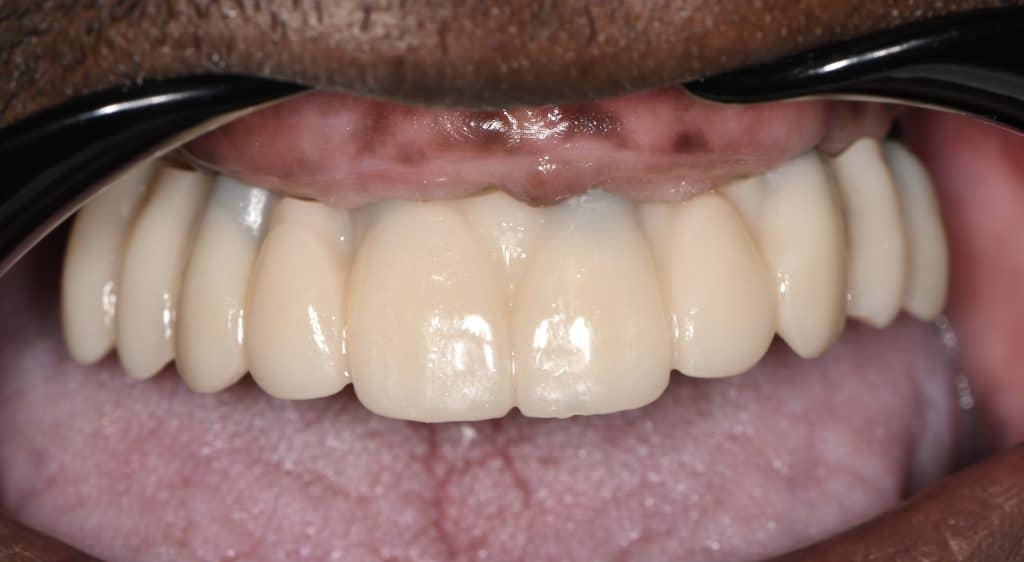

here a case where a full mouth réhabilitation was done by placing 6 implants

multiunit abutement were placed and a temporary bridge also was made for emergence profile shaping